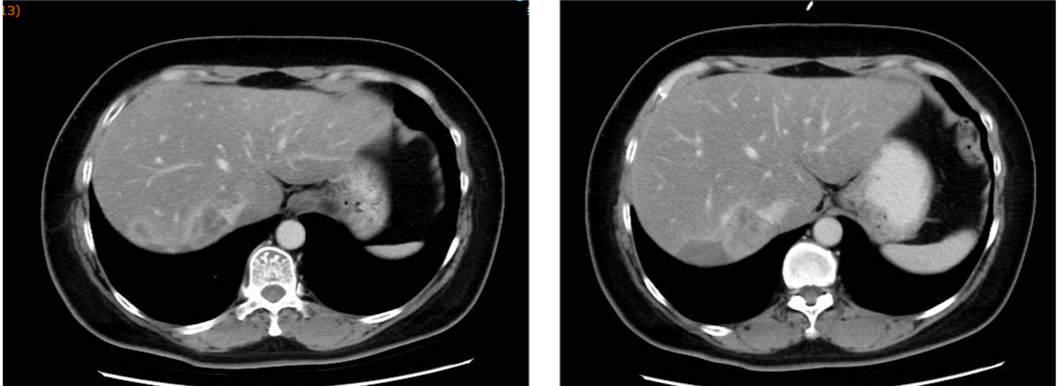

▌影像学检查:

2013年6月30日腹部CT:肝右后叶病灶并肝内多发子灶,考虑M,病灶总范围8.0*5.8cm,其病灶周围可见多发异常廓清子灶(4-5个),最大约1.6cm;

图1. 腹部CT